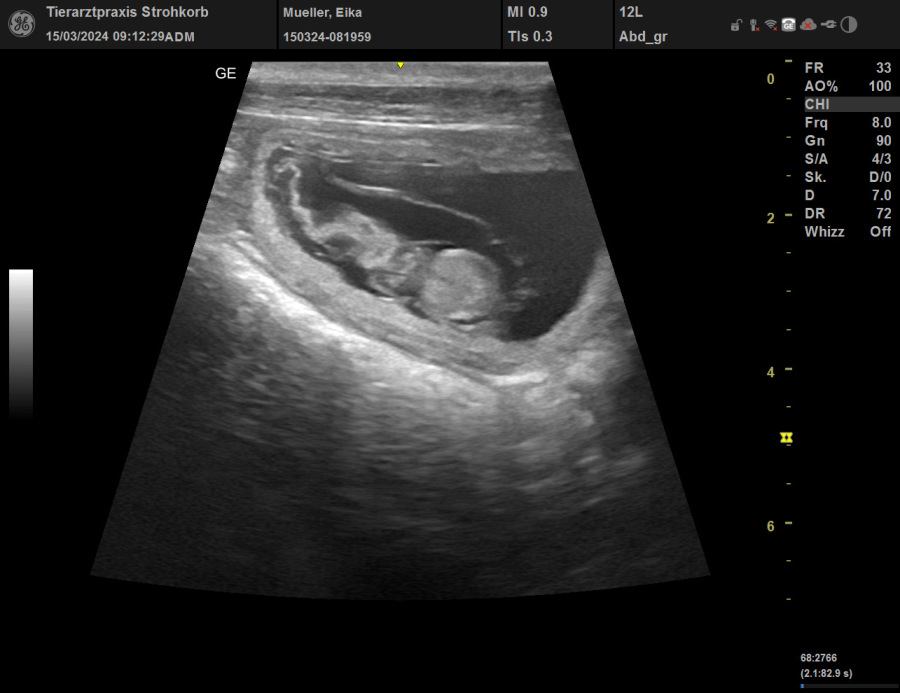

15.03.2024      Eika ist laut Ultraschall tragend. Wir freuen uns auf unseren ersten Wurf im

Kapellenteich.